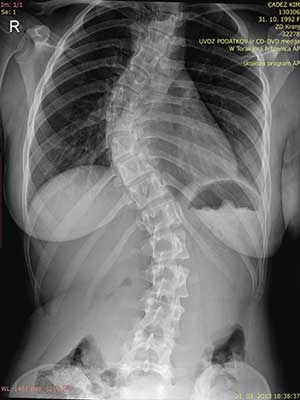

Pojdimo nazaj v leto 2004. 20 let nazaj, ko so mi, kot večini na sistematskem pregledu ugotovili začetek skolioze. Sledil je obisk pri ortopedu, slikanje in potrditev diagnoze začetka skolioze.

V tistem trenutku ni bila ta diagnoza nič posebenga, skolioza je bila še v začetku saj je merila 28°v prsnem delu in 15° ledvenem delu (Ko danes berem te stopinje… skolioza je že konkretno napredovala in pametno bi bilo takoj predpisati vaje in steznik). Takrat so nam naročili, naj se vrnemo čez pol leta. Da bodo opazovali.

Moja hrbtenica leta 2004

Nismo ji/mi posvečali prevelike pozornosti, ker tudi ortopedi niso pokazali skrbi. In tako je minilo pol leta, ko sem zopet slikala svojo hrbtenico.